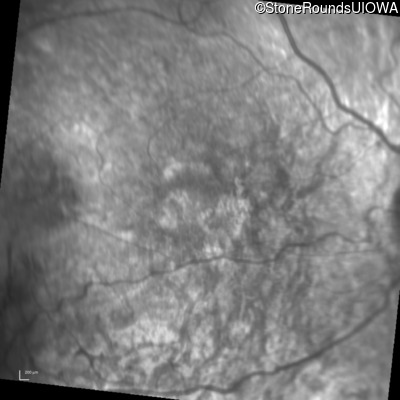

Infrared Fundus Photograph - Right - 20/100

Exemplar